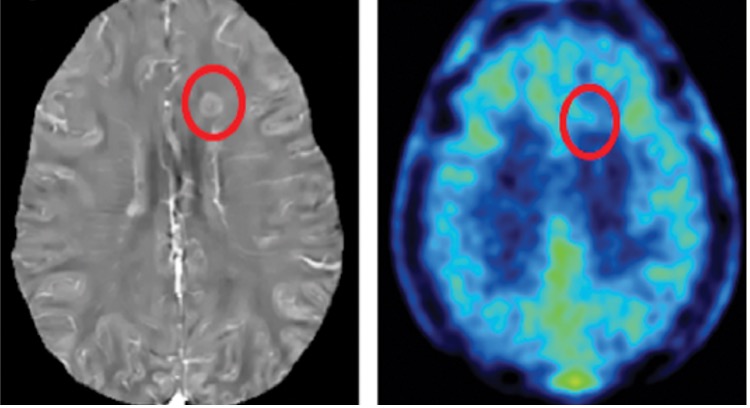

Measure hemorrhages, including cerebral cavernous malformation (CCM) and microbleeds. QSM is a quantitative biomarker for monitoring CCM disease activity and response to treatments. Traditional MRI (T2 weighted, below left) does not provide a quantitative measure of bleeding in CCM. QSM (below right) provides a quantitative measure of the total magnetic moment for monitoring the CCM lesion.